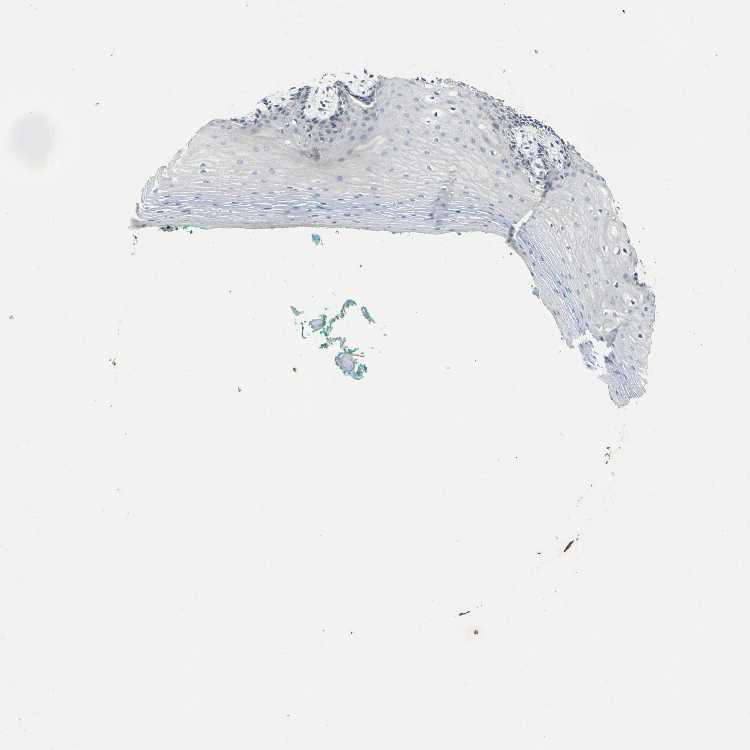

TISSUE PRIMARY DATA ORAL MUCOSA Show tissue menu

ORAL MUCOSA - Antibody stainingi

Antibody staining in the annotated cell types in the current human tissue is reported as not detected, low, medium, or high, based on conventional immunohistochemistry profiling in selected tissues. This score is based on the combination of the staining intensity and fraction of stained cells.

Each image is clickable and will lead to virtual microscopy that enables deeper exploration of all samples and also displays staining intensity scores, fraction scores and subcellular localization as well as patient and tissue information for each sample.

Antibody HPA014377

Squamous epithelial cells Not detected